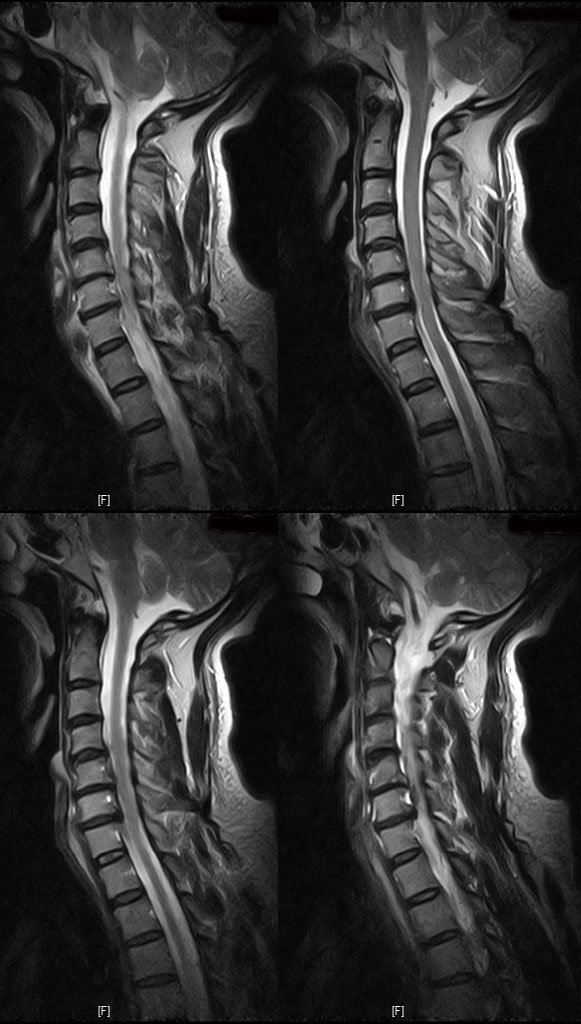

Ű 169 65 52 ˰Ե ͳ ˻ڷ õ ش 1C., 1C.ڵӸ 1C.ٸǷ 2C.ڽ÷ 3C. 4C.5C.ھ, հ 5C.6C.ڰ հ ̳ 6C.ھ Ḳ 6C.ڻ 6C.7C.ھ հ ̳ 1T.ڼո 1T.ڼհ ü ̳ 1T.꿪 ĵ 5T.氣 5T.ھ ȯ 6T., 6T.ټ 6T.ٽƮ 6T.꿪 ĵ 7T.˾ 10T.ٸǷ 3L.̻ 3L. 3L.ڹ 3L. 4L Һ Һ 4L. ̻ 4L.° ()ũ( ߰Ż) ߺ ༺ ũ ũ(߰) Ը ũ(߰Ż)ġ, հ , ġ, , Ḳ ġ Ǵ ġ ô , 㸮 ̳ ġ ħ , dz, , Ǵ ġ Ƿ ġ γ Ȱ ϰ Ѱ . ..( ⰨȰó Ҷ ִ) 1)()ũ( ߰Ż) 2)()ũ( ߰) --㳻-- ** ڰ , *** ġغ ϰ ֻ̿ °Դٰ , ȸԲ MRI ġ ɼ ſ ٰ Ͻð 迵ռ̳ Բ Ͻö ϼ̽ϴ. |